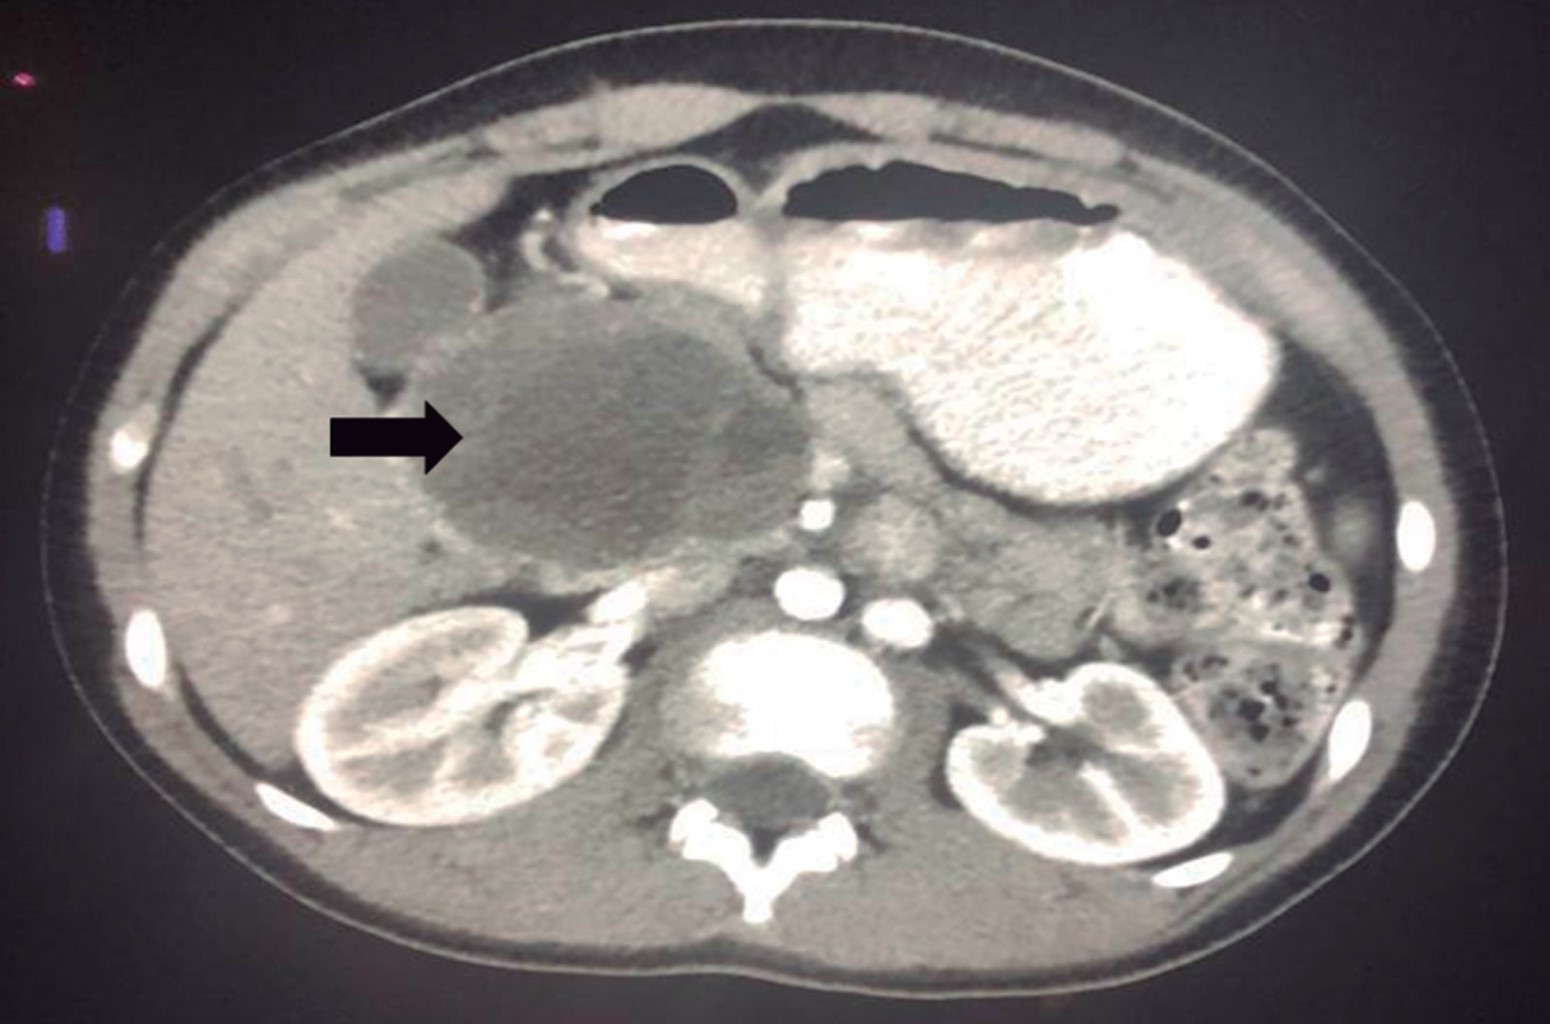

Se realizan estudios de imagen: ecografía abdominopélvica compatible con lesión tumoral heterogénea retroperitoneal con áreas quísticas en la vecindad de la cabeza del páncreas que mide 6 × 10.1 cm por encima del área suprarrenal; tomografía computarizada (TC) de abdomen y pelvis simple y con contraste endovenoso, se evidencia lesión tumoral heterogénea tabicada con captación del contraste en la periferia y tabiques, presencia de áreas de menor densidad quísticas localizada en la cabeza del páncreas de contornos bien delimitados que miden 5.9 × 6.7 × 7 cm; cuerpo y cola pancreática sin alteraciones, sin dilatación del conducto de Wirsung, sin presencia de obliteración de la grasa perivascular en arteria mesentérica superior ni del eje esplenoportal, ni evidencia de adenomegalias retroperitoneales (Figura 1).

Figura 1